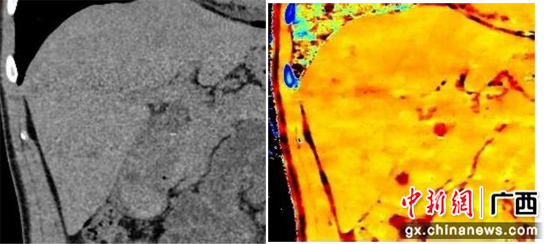

左图为常规图像,右图为原子序数图。原子序数图可见胆囊阴性结石。南溪山医院供图 而且,该台CT配备的双层探测器结构能做到同时、同源、同向、同步的“四同”成像,不需要选择特定的能谱序列,所有扫描信息都是能量扫描,实现了从解剖成像到功能和分子水平成像的跨越。 CT从传统黑白影像时代迈入彩色多参数诊断新时代,这不仅意味着诊断数据的丰富,更使得原来只基于CT值的组织密度分析判断,变成更为精准的多参数、多维度分析模式,为CT诊断带来了颠覆性改变。此次新CT的投入使用,使得实力雄厚的南溪山医院医学影像科团队再添利器,将造福更多患者,真正实现一步到位的精准诊疗。 |